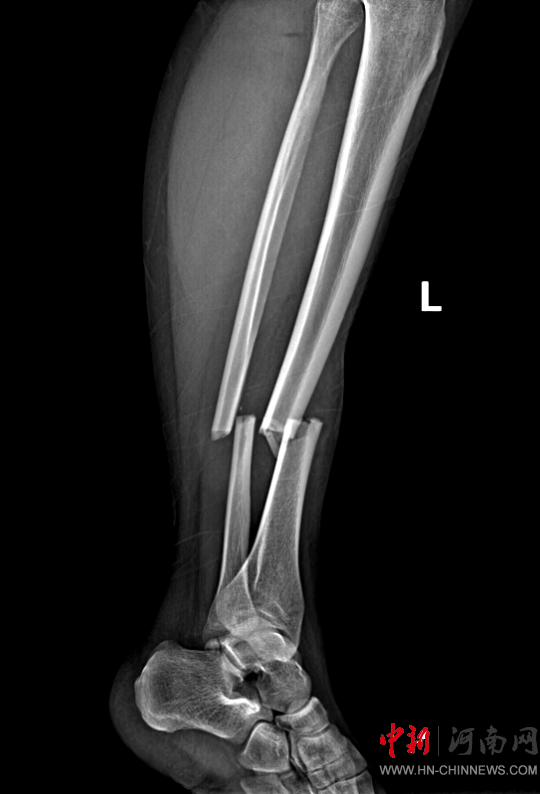

患者,女,32歲,車禍傷,到達(dá)確山縣人民醫(yī)院急診科創(chuàng)傷中心救治時血壓80/45mmHg,心率115次/分,處于昏迷、休克狀態(tài),病情危重。急診科迅速啟動創(chuàng)傷中心急救綠色通道,醫(yī)護(hù)人員立即展開搶救,積極抗休克治療的同時,聯(lián)系神經(jīng)外科、胸外科、急診重癥監(jiān)護(hù)室緊急會診,同時快速CT、床旁FAST檢查明確診斷。通過一系列急救措施,患者的休克狀態(tài)稍微好轉(zhuǎn),經(jīng)多學(xué)科會診后明確診斷為:多處損傷并失血性休克、彌漫性軸索損傷、蛛網(wǎng)膜下腔出血、腦挫傷、股骨及脛腓骨粉碎性骨折、多發(fā)肋骨骨折并肺挫傷、腰椎骨折。ISS評分高達(dá)50分,死亡率極高,患者病情危重,立即送入急診重癥監(jiān)護(hù)室進(jìn)行高級生命支持治療。

患者病情好轉(zhuǎn)后,該院急診科主任岳春彥和創(chuàng)傷治療團(tuán)隊(duì)為患者制定了詳細(xì)的手術(shù)規(guī)劃,傷后第10日,患者在全身麻醉下進(jìn)行“左股骨粉碎骨折及脛骨粉碎骨折髓內(nèi)釘內(nèi)固定術(shù)+骨移植術(shù)、腓骨骨折復(fù)位內(nèi)固定術(shù)”,病情平穩(wěn)后轉(zhuǎn)入急診科病房治療,切口愈合后,患者轉(zhuǎn)入康復(fù)醫(yī)學(xué)科進(jìn)行腦功能康復(fù)和下肢關(guān)節(jié)康復(fù)治療。目前,患者能夠與人正常溝通交流,左下肢關(guān)節(jié)功能也恢復(fù)良好,已出院。